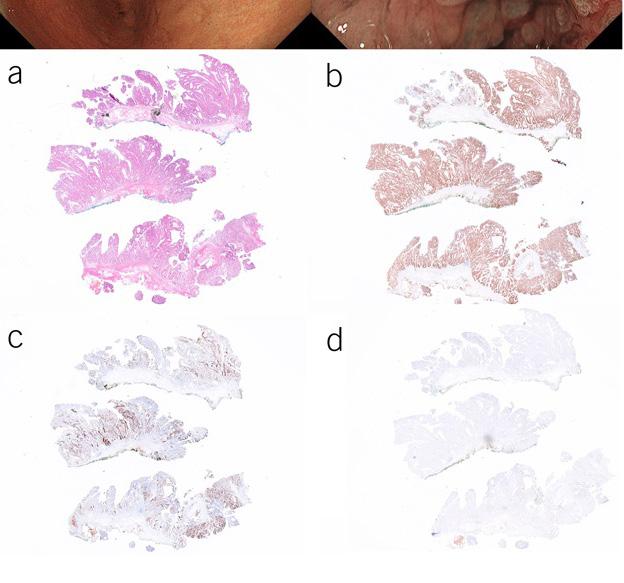

40 AJG

A new ACG Guideline and podcast on H. pylori Infection by Chey, et al., & Natural History of Indeterminate Liver Nodules in Patients with Advanced Liver Disease by Singal, et al